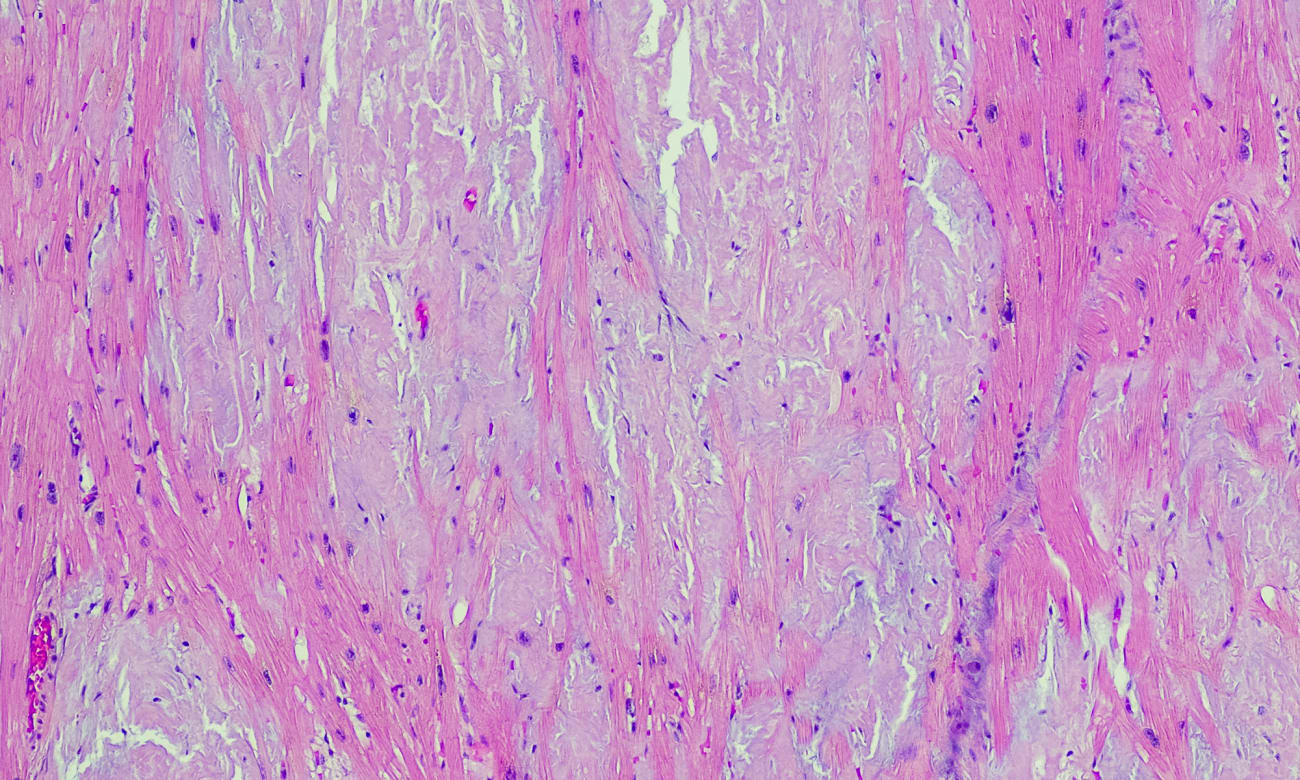

Until recently, patients with suspected or confirmed cardiac amyloidosis had few options. The only way for physicians to diagnose the condition was to search for the misfolded proteins through tissue biopsy, often times cardiac — a procedure typically offered at tertiary care hospitals. For one of the most common subtypes, known as AL or light chain amyloidosis, treatments such as chemotherapy, immunotherapy and stem cell transplants came with numerous side effects. For the other major subtype, known as ATTR or transthyretin cardiac amyloidosis, no disease-modifying pharmaceutical therapies existed.